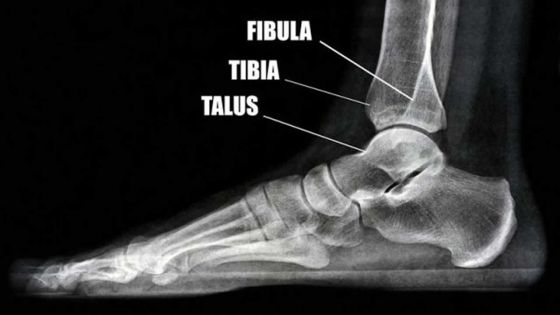

Elle a eu le tibia écrasé dans un accident de la route : les difficultés de Yasmine pour obtenir une pension d’invalidité

Explik Ou Ka

Elle a eu le tibia écrasé dans un accident de la route : les difficultés de Yasmine pour obtenir…